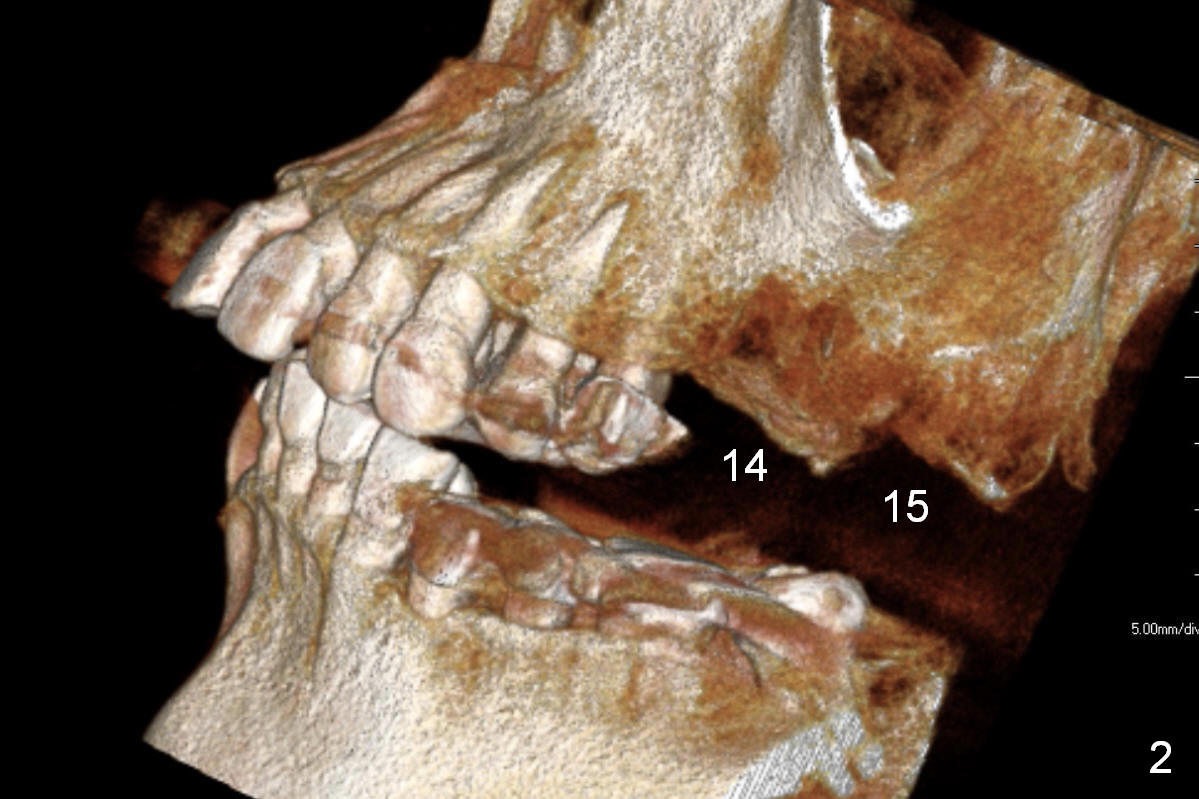

On the other hand, her occlusion is out of order. The teeth #2,14,15,30 and 31 are missing with #3 supraeruption and deep anterior overbite and overjet (Fig.1,2). This may lead to TMD. Alginate impression will be taken for fabrication of night guard or occlusal guard to raise vertical height. If this helps, implants are placed (Fig.3-6), followed by limited or comprehensive ortho to intrude #3, to permanently change her occlusion.